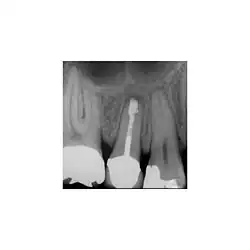

Résection apicale

Les objectifs de la résection apicale sont :

- retirer une partie de la racine qui ne pourrait être désinfectée ou/et remplie avec un matériau de remplissage de canal et dont les contenus peuvent avoir causé ou maintenu une inflammation,

faciliter l'accès pour la création d'une préparation de terminaison radiculaire, en vue d'un remplissage de terminaison radiculaire. L'apex doit être réséqué avec peu ou pas de biseau. Le procédé lui-même est rarement utilisé, et seulement quand on a considéré que le canal radiculaire a été traité de façon satisfaisante, et bien rempli.

- Préparation et remplissage de terminaison radiculaire

La préparation de la terminaison radiculaire est pratiquée après la résection de l'apex. Cela doit suivre les contours du système canalaire et être dans l'axe du (des) canal(aux). L'objectif du remplissage de terminaison canalaire est de remplir cette cavité et de fermer toute communication du canal radiculaire aux tissus péri radiculaires. Un matériau de remplissage est placé dans la cavité de la terminaison radiculaire. L'amalgame n'est plus le matériau de choix.